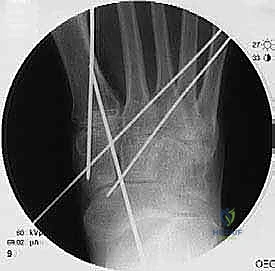

لضمان التحام العظام لتصبح عظمة واحدة صلبة، يجب تثبيتها بقوة هائلة حتى لا تتحرك أثناء فترة الشفاء. يتم استخدام مسامير معدنية متطورة (Screws)، أو شرائح معدنية خاصة (Plates)، أو دبابيس طبية متخصصة (Staples) مصنوعة من التيتانيوم الآمن على الجسم.

7. الإغلاق والضماد

بعد التأكد التام من وضع العظام وثباتها باستخدام جهاز الأشعة السينية داخل غرفة العمليات (C-Arm)، يتم إغلاق الشقوق الج